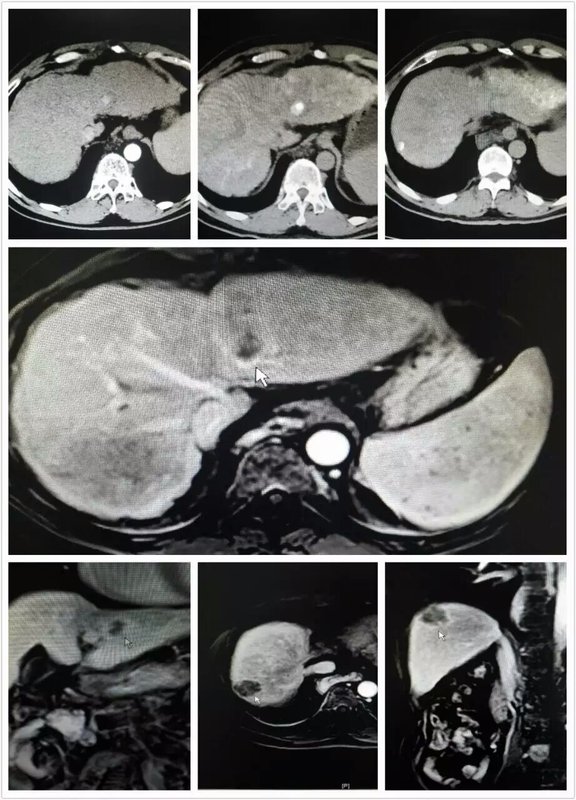

多發(fā)性小肝癌的綜合治療,結(jié)合TACE及超聲及CT下的PMCT(患者曾于3年前因同樣小肝癌予以上述同樣治療)。充分發(fā)揮多重影像在介入微創(chuàng)治療中的優(yōu)勢(shì)。安全有效、可重復(fù)性強(qiáng)。 徐醫(yī)附院介入科腫瘤微創(chuàng)治療科介入血管外科許偉~健康保護(hù)神